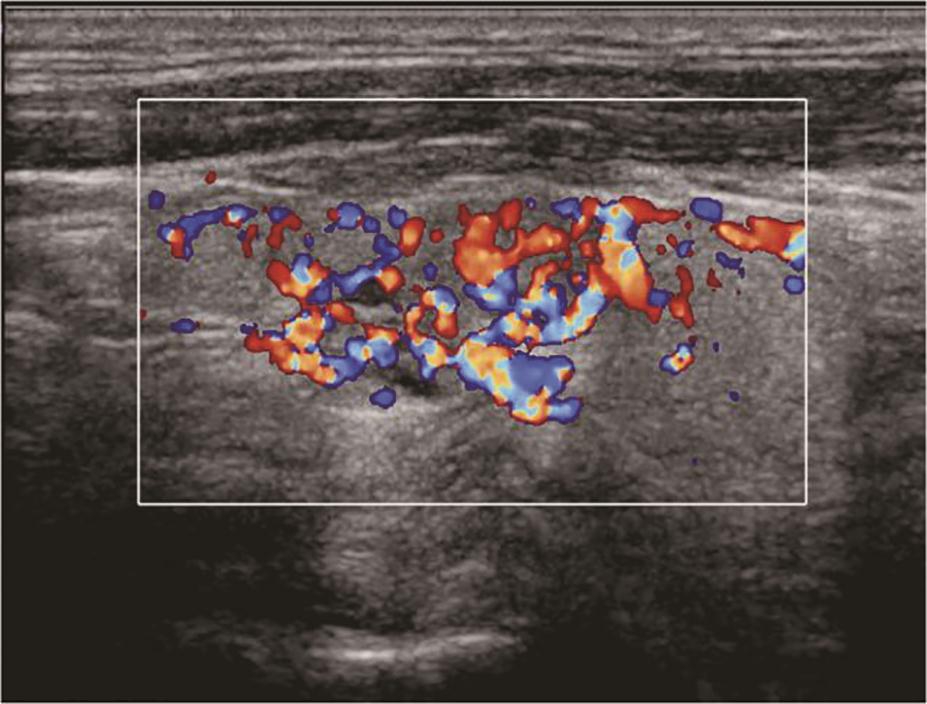

(五)Graves病

甲状腺呈弥漫性、对称性增大,包膜规则。腺体回声因病程和治疗情况而有所不同。未经治疗者,腺体回声均匀减低,少数呈散在、局灶性减低;病程长及反复发作者,腺体回声正常或稍强。腺体内可见多个管状无回声区(血管扩张)。彩色多普勒显示甲状腺内血流信号极为丰富,呈“火海征”(图3)。频谱多普勒可见甲状腺上、下动脉血流速加快,收缩期峰值流速多超过70cm/s(正常为30cm/s)(图4)。

图3右侧颈部纵切面:甲状腺右叶腺体血流信号丰富,呈“火海征”